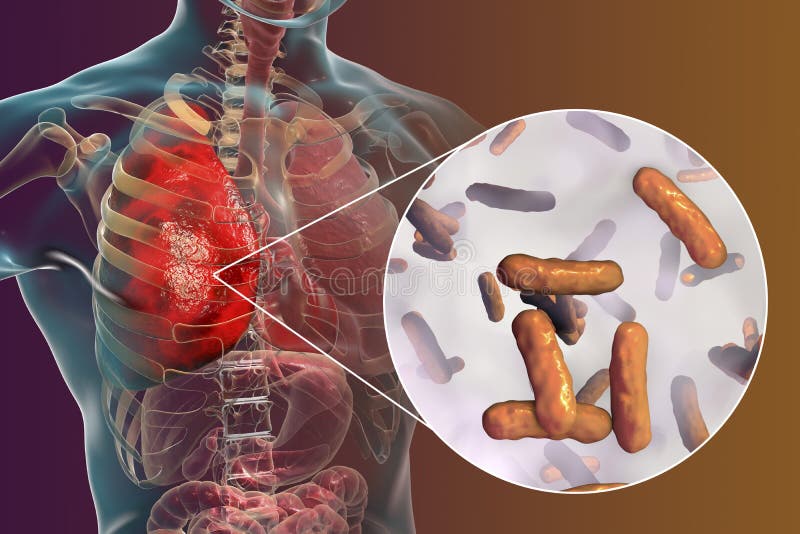

Фотографии бактерий, вызывающих бактериальные пневмонии у животных

Раздел: Другие животные